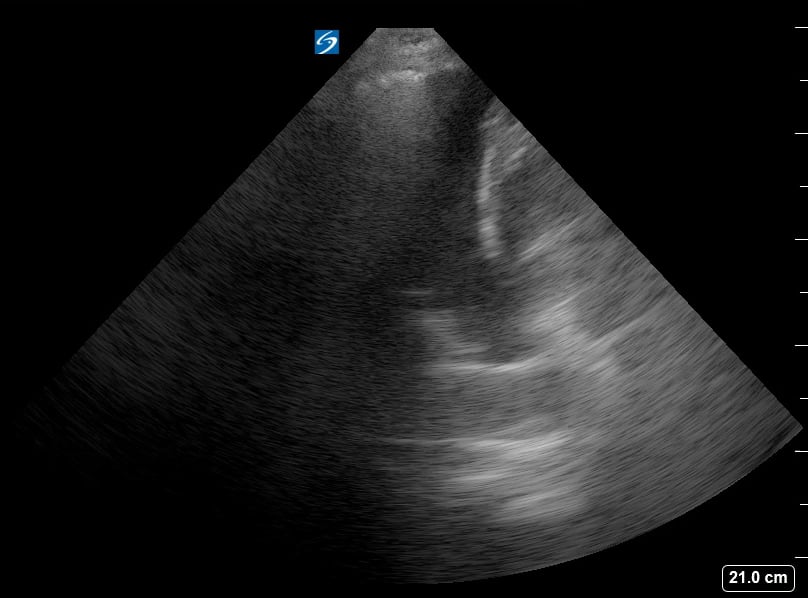

Lung consolidation in medical ultrasound refers to the solidification of lung tissue due to the accumulation of fluid, cells, or other substances, replacing the air within the alveoli. This pathological change commonly indicates conditions like pneumonia or atelectasis. On ultrasound, consolidated lung appears hyperechoic (bright) with a tissue-like echotexture, often resembling the liver (hepatization).

Identifying lung consolidation via ultrasound is crucial for rapid diagnosis and management in acute care settings. This non-invasive imaging technique allows clinicians to visualize air bronchograms (air-filled bronchi within consolidated tissue) and pleural effusions, aiding in differentiation from other lung pathologies. Ultrasound offers a portable and radiation-free alternative for bedside assessment of lung parenchyma, optimizing patient care.